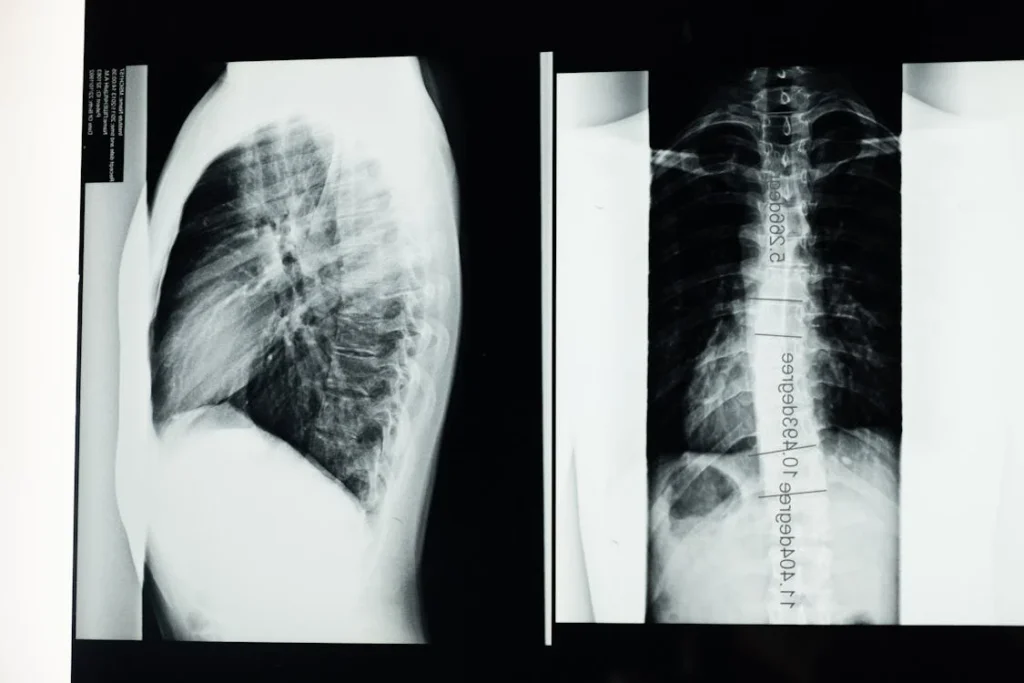

Gerincgörbület vizuális megjelenése

A scoliosis egyik legjellegzetesebb tünete maga a gerincgörbület, amely szabad szemmel is láthatóvá válhat. A görbület leggyakrabban a mellkasi vagy az ágyéki szakaszon alakul ki, és oldalirányú elhajlásként jelenik meg. Súlyosabb esetekben a görbület már állás közben is jól látható, de enyhébb esetekben csak előrehajláskor válik észrevehetővé.

Az előrehajlás tesztje, amelyet gyakran használnak az orvosok a gerincferdülés diagnosztizálására, segíthet felfedni a görbületet. Ebben a helyzetben a gerinc íve jobban láthatóvá válik, és a test aszimmetriái is kifejezettebbé válnak. Ez különösen a serdülők esetében fontos szűrővizsgálat, mivel a scoliosis gyakran ebben az életkorban fejlődik ki.

A gerincgörbület mértéke változó lehet. Enyhe esetekben a görbület csak néhány fokos eltérést jelent a normális gerinctartáshoz képest, míg súlyosabb esetekben akár 40-50 fokos görbület is kialakulhat. Minél nagyobb a görbület, annál valószínűbb, hogy a beteg fájdalmat és mozgáskorlátozottságot tapasztal.